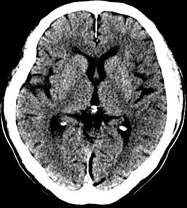

如上圖所示,相鄰的三張軸位圖像未見明顯異常,根據(jù)傳統(tǒng)軸位圖像很難得到準確的臨床診斷。

同一病人利用容積數(shù)據(jù)進行三維處理后,高品質(zhì)MPR和三維圖像上則清晰顯示了縱向排列的腹腔干與腸系膜上動脈相鄰近,血管發(fā)生變 異,近端血管閉塞,為臨床提供了精確的診斷信息。